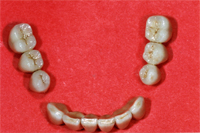

Im Labor wählt der Techniker die entsprechenden Stumpfaufbauten, die in den Implantaten im Mund fest eingeschraubt werden (Abb. 5). Zu diesem Zeitpunkt sind die drei provisorischen Druckknopfimplantate bereits entfernt, damit die Metallkeramikwerkstücke von Abb. 6 im Mund einprobiert werden können.

|

Zweieinhalb Monate nach der Implantation werden am 19. September 2006 die drei Brücken (Abb 6) definitiv im Mund zementiert (Abb. 7). Als der Patient wenig später zur Nachkontrolle kommt, antwortet er mir auf die Frage, wie er mit der neuen Situation zurecht kommt, ganz einfach mit den Worten: